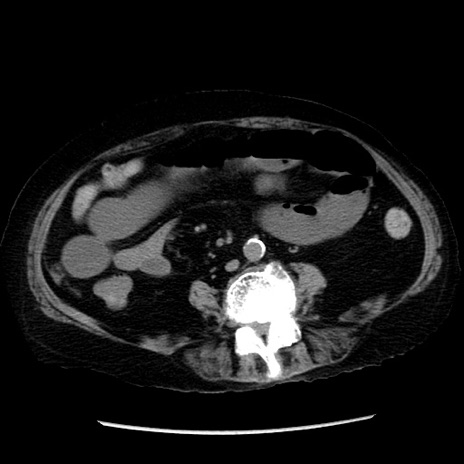

症例14(横断像)

【症例】 90歳代女性

【主訴】 腹痛・嘔吐

【現病歴】今朝から左側腹部痛を認めた。 経過観察していたが、嘔吐を認めたため来院。

【既往歴】 子宮癌術後

【身体所見】 意識清明、BP 127/54mmHg、P 98bpm Sp02 95%(RA)、BT 35.8°C、腹部平坦・軟腸ぜん動音聴取良好、右下腹部圧痛(+) 反跳痛なし

【データ】WBC 9800、CRP 0.46